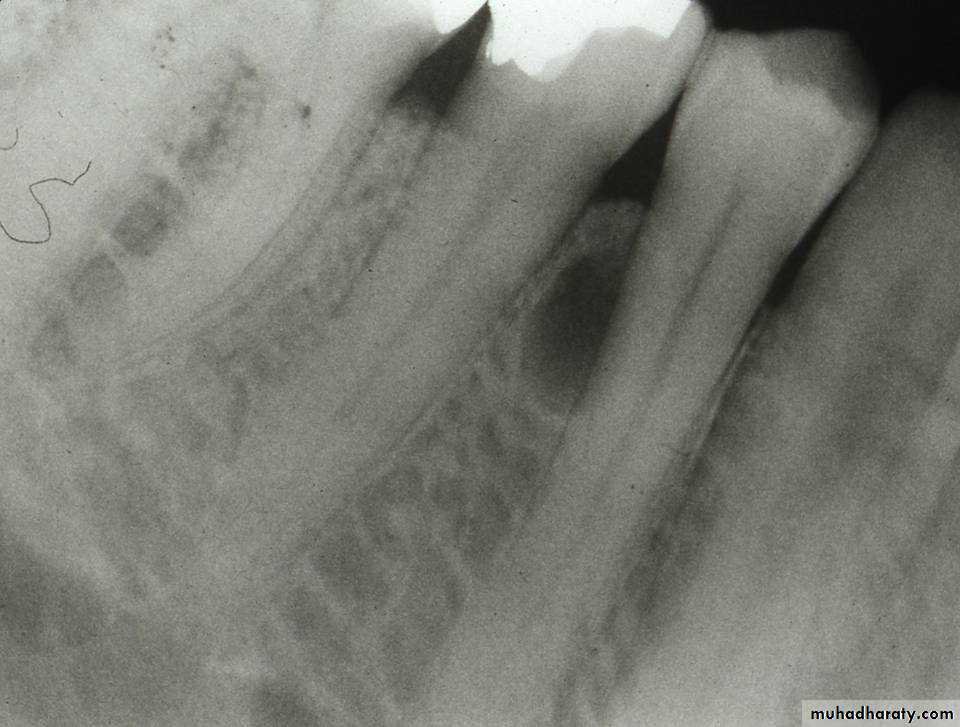

Lateral periodontal cyst

These un common intraosseous cysts are developmental and form beside a vital tooth.They are usually seen by chance in routine radiograph.

Resemble other OC radiographically, apart from its position near the crest of the ridge.

Cause no symptoms but can erode through the bone to extend in to the gingiva.

Respond to enucleation.

The related tooth can be retained if healthy